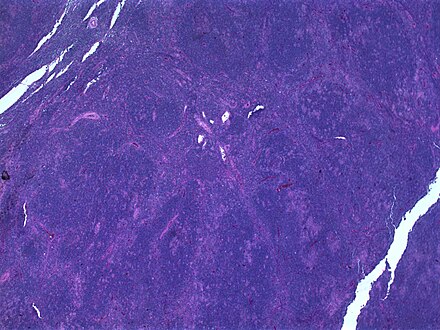

Popcorn cell in nodular lymphocyte predominant Hodgkin lymphoma - very high mag cropped.jpg

Micrograph of a lymph node biopsy showing nodular lymphocyte predominant Hodgkin lymphoma, with the Reed–Sternberg cell variant that has a popcorn-shaped nucleus (left-bottom of image). H&E stain.

NLPHL is an uncommon sub-type of Hodgkin lymphoma, making up 5-10% of Hodgkin lymphomas.[3] It is distinguished from classic Hodgkin lymphoma by the presence of CD20 positive lymphocyte predominant cells, also known as popcorn cells due to their polylobated nuclei, which look like popcorn.[3][4][5]

The characteristics of NLPHL differ from classical Hodgkin lymphoma (cHL).[9] Lymphocyte predominant (LP) ("popcorn") cells are present embedded in nodules consisting of B cells[10] and other reactive cells (mainly reactive T cells).[9] Reed-Sternberg and Hodgkin (RSH) cells are rarely seen, and immunohistochemistry shows a different pattern on the malignant cells; RSH cells typically express CD15 and CD30, whereas LP cells lack expression of these markers, but express B cell markers like CD20, CD22, and CD79a and also express the common leukocyte antigen CD45, which is uncommon on RSH cells.[9] The LP cells have scant cytoplasm and one folded or multilobated nuclei with prominent, mostly basophilic nucleoli.[10] Expert pathology review of multiple morphologic and immunophenotypic features[10] including the use of immunohistochemistry is essential.[11][12]